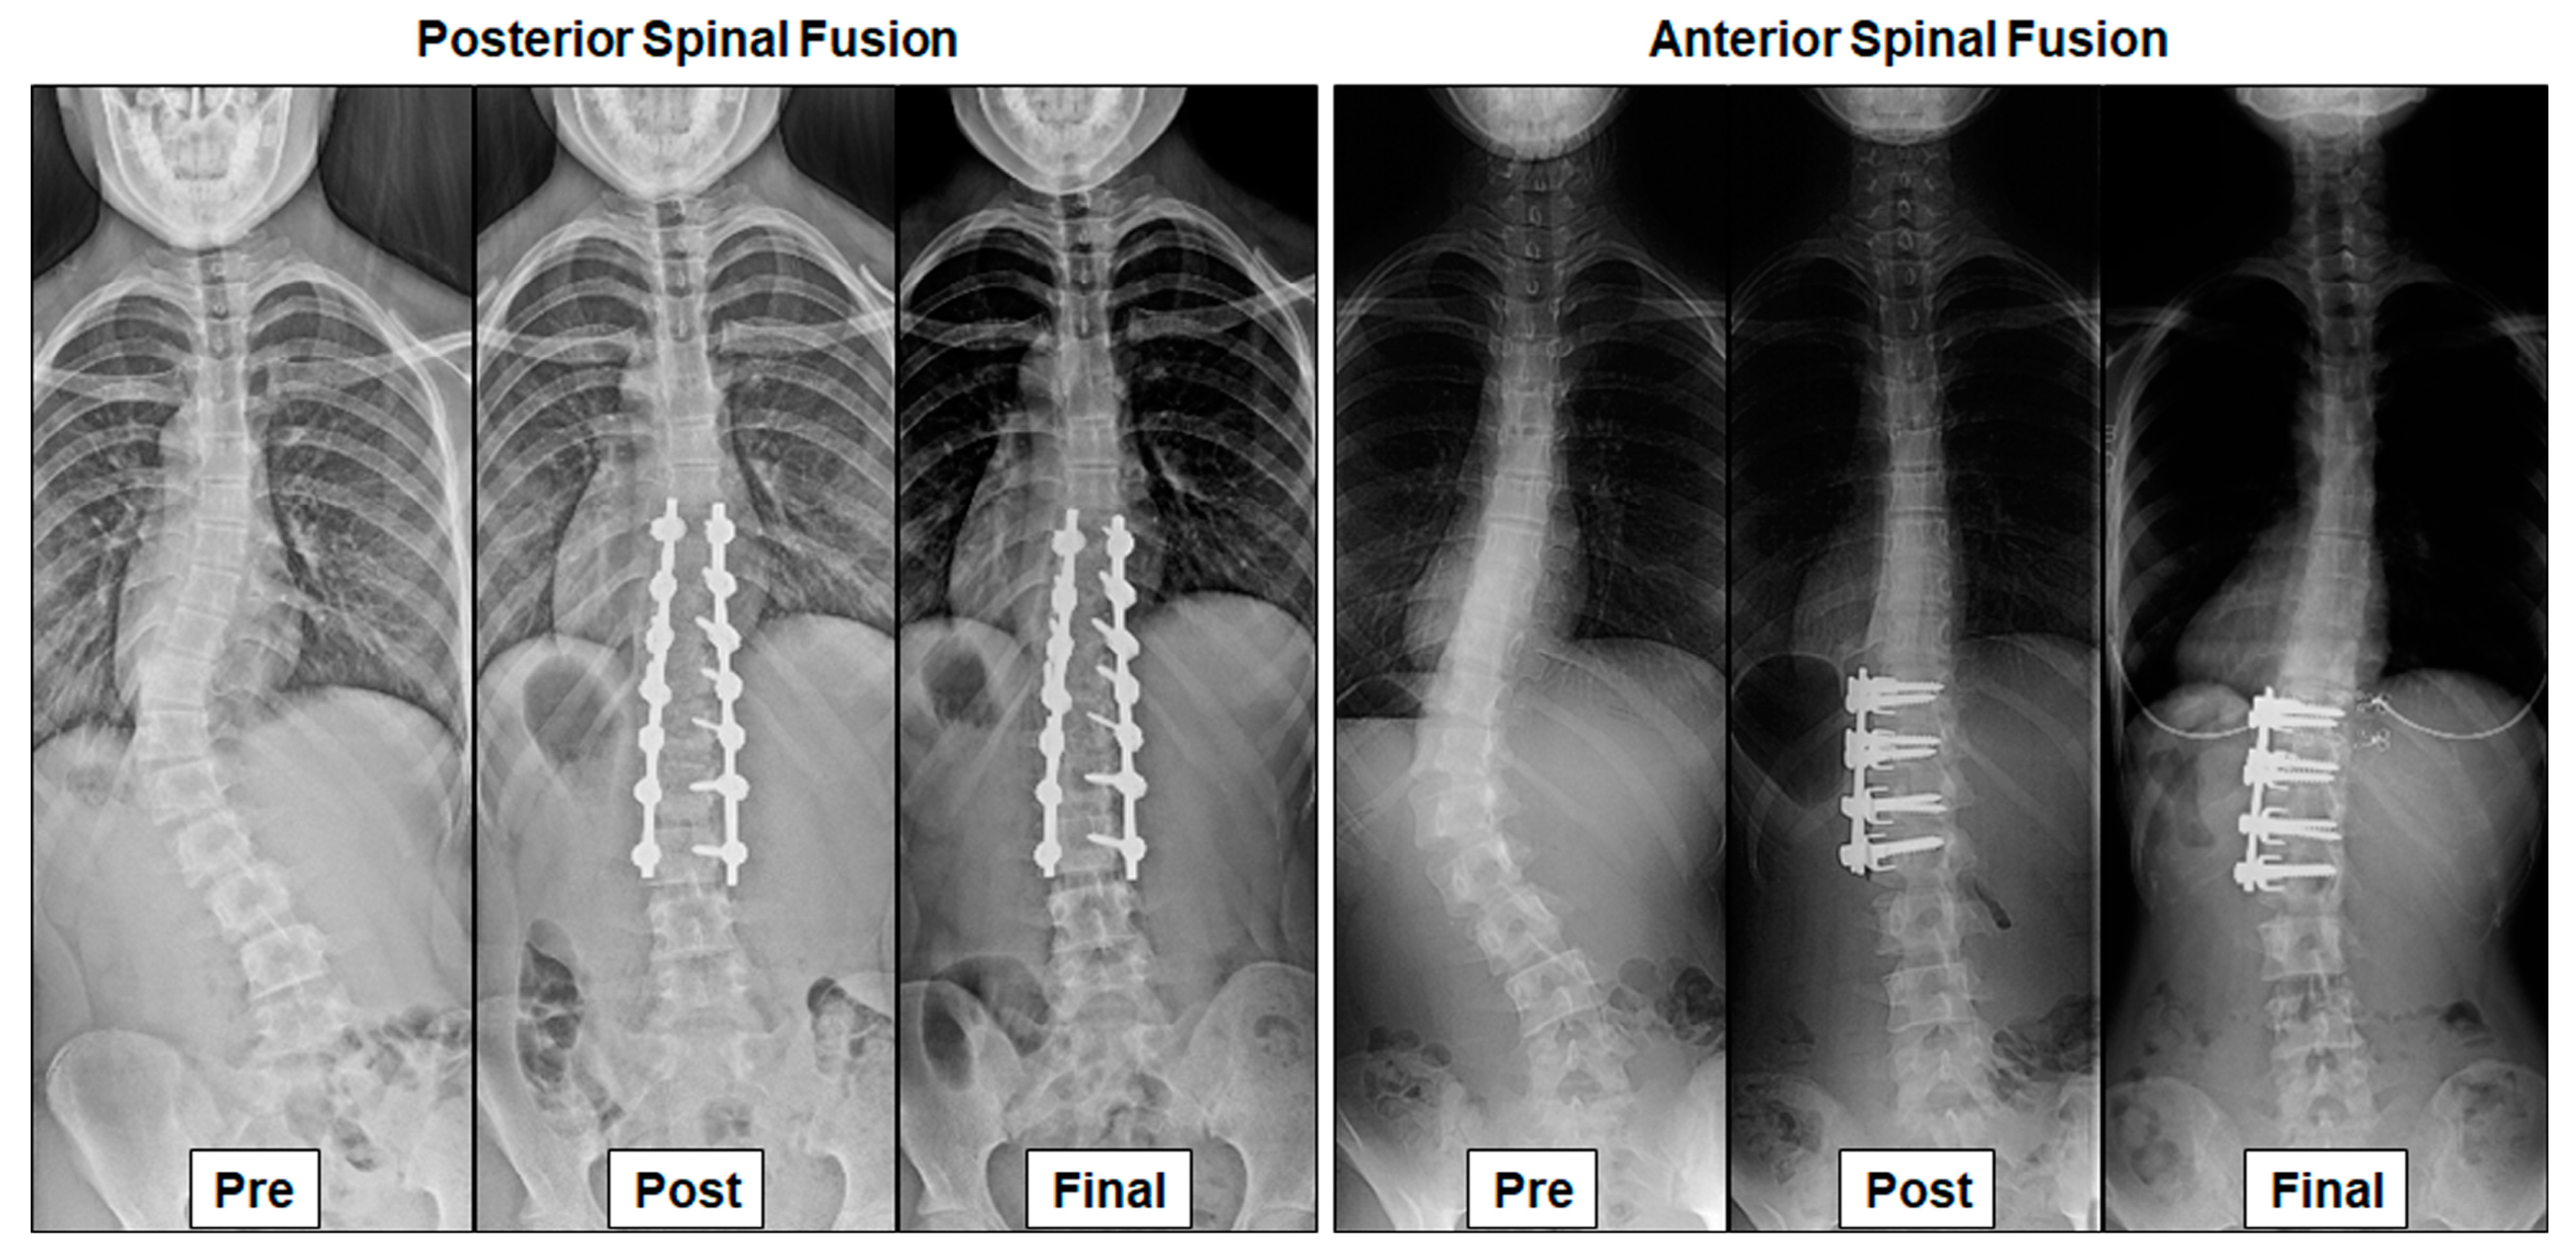

- (Posterior spinal fusion) A thirteen-year-old girl with a preoperative thoracolumbar (TL) curve of 48° improved to 8° 2 years after surgery. Lower instrumented vertebra translation from the central sacral vertical line (LIV translation) was 32 mm preoperatively and improved to 16 mm at the final follow up.

- (Anterior spinal fusion) A fourteen-year-old girl with a preoperative TL curve of 53° improved to 10° 18 years after surgery. LIV translation improved from 49 mm preoperatively to 11 mm at the final follow-up.